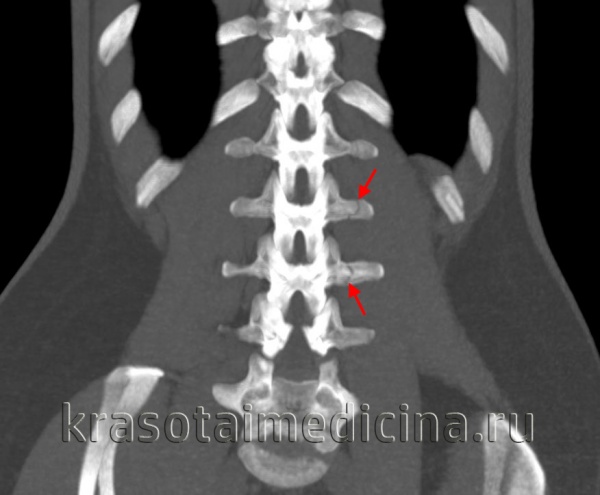

КТ грудного и поясничного отделов позвоночника. Перелом поперечного отростка 2-го и 3-го поясничного позвонка без смещения.